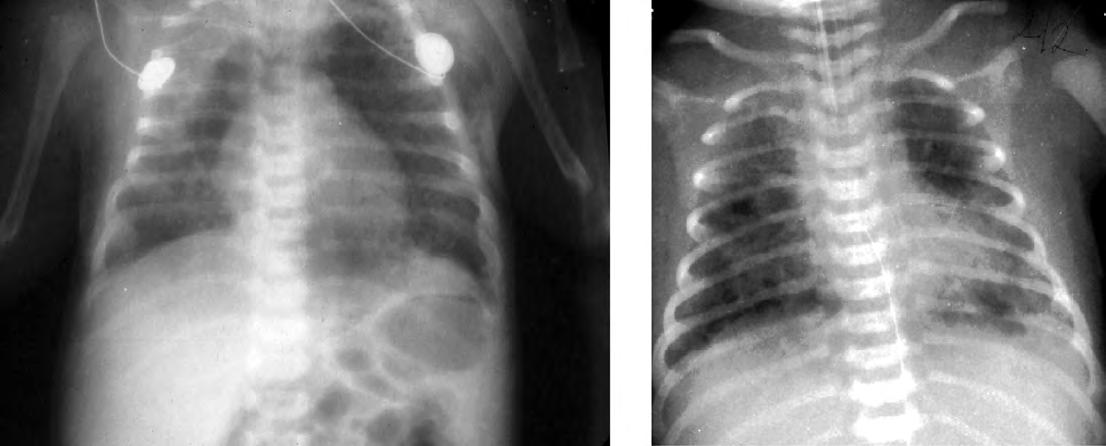

El patrón radiológico es muy variable y no guarda buena correlación con la gravedad clínica. Inicialmente se caracteriza por zonas infiltrativas con imágenes hiliofugales de intenso refuerzo junto con áreas de hiperinsuflación, y aire extraalveolar (Fig. 2.17.2). En las formas más graves suele predominar la imagen de atelectasia, edema y bajo volumen pulmonar probablemente por la inactivación del surfactante y fallo cardiaco relacionado con el episodio asfíctico concomitante.